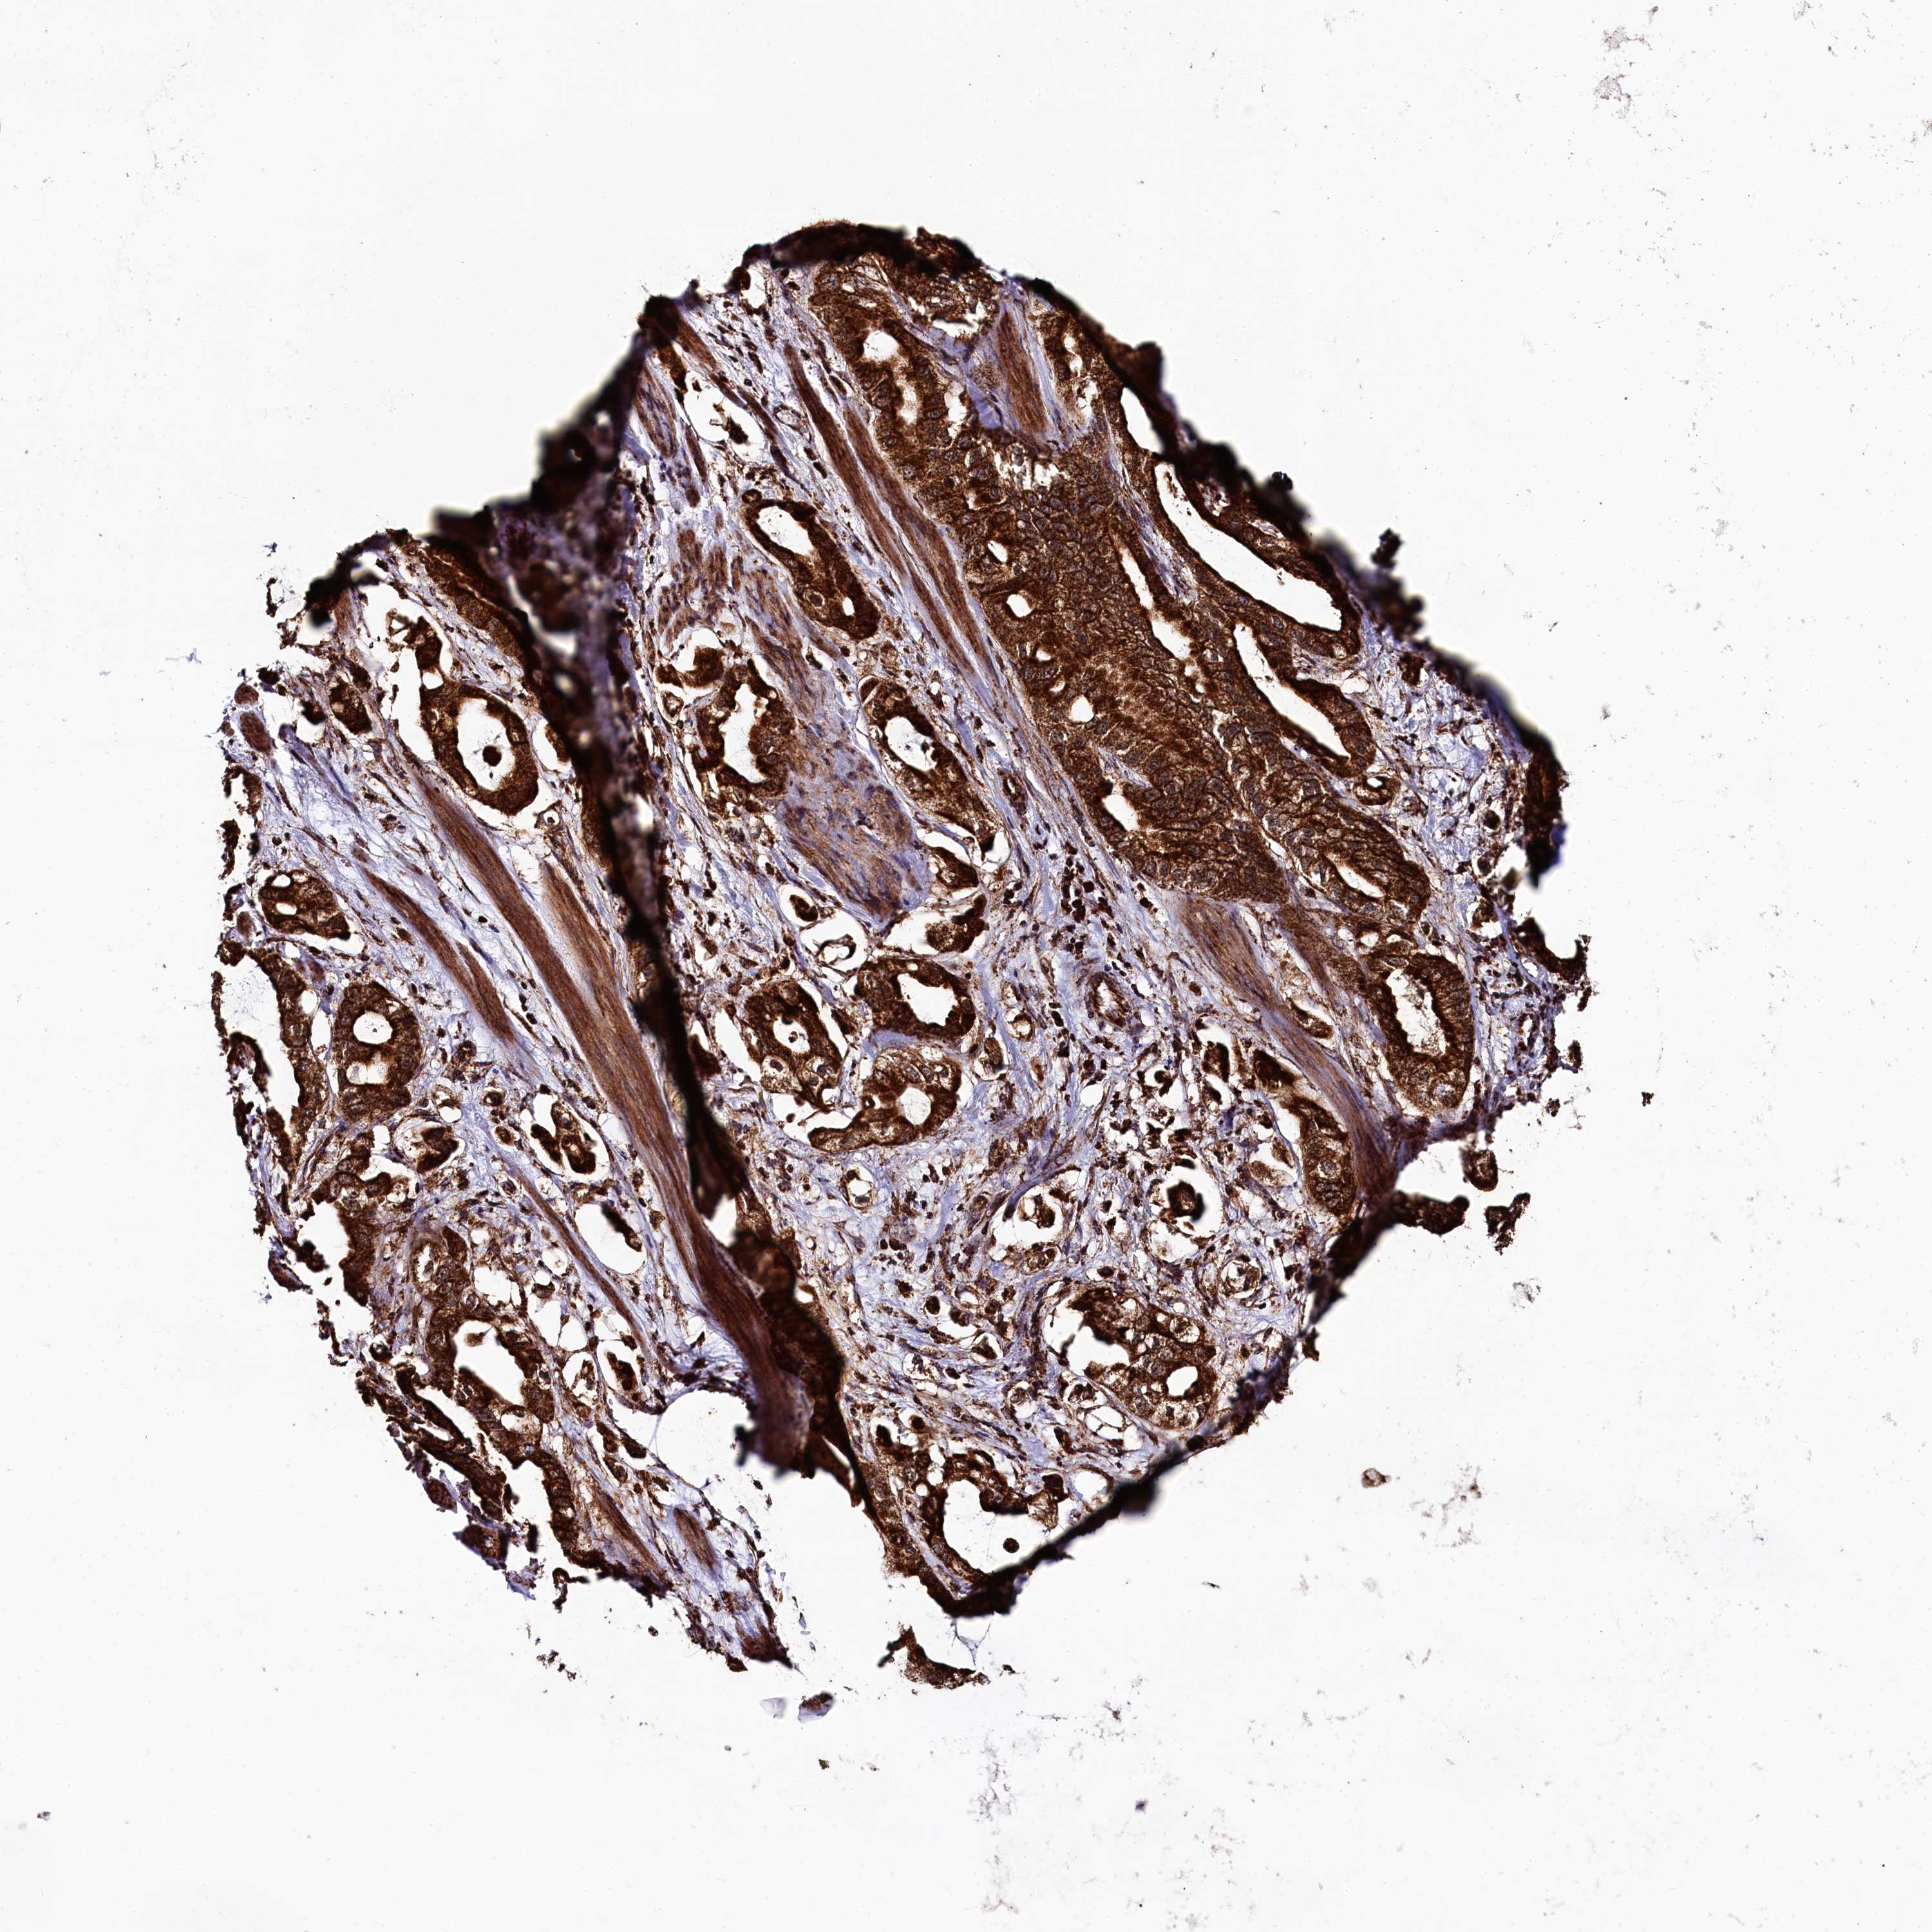

STOMACH CANCER - Protein expressioni

A mouse-over function shows sample information and annotation data. Click on an image to view it in a full screen mode. Samples can be filtered based on level of antibody staining by selecting one or several of the following categories: high, medium, low and not detected. The assay and annotation is described here.

Note that samples used for immunohistochemistry by the Human Protein Atlas do not correspond to samples in the TCGA dataset.

Antibody stainingi

Antibody staining in the annotated cell types in the current human tissue is reported as not detected, low, medium, or high, based on conventional immunohistochemistry profiling in selected tissues. This score is based on the combination of the staining intensity and fraction of stained cells.

Each image is clickable and will lead to virtual microscopy that enables deeper exploration of all samples and also displays staining intensity scores, fraction scores and subcellular localization as well as patient and tissue information for each sample.

Antibody HPA040416

Antibody HPA040434

Staining

High

Medium

Low

Not detected

Intensity

Strong

Moderate

Weak

Negative

Quantity

>75%

75%-25%

<25%

None

Location

Nuclear

Cytoplasmic/membranous

Cytoplasmic/membranous,nuclear

Adenocarcinoma, NOS

Adenocarcinoma, High grade